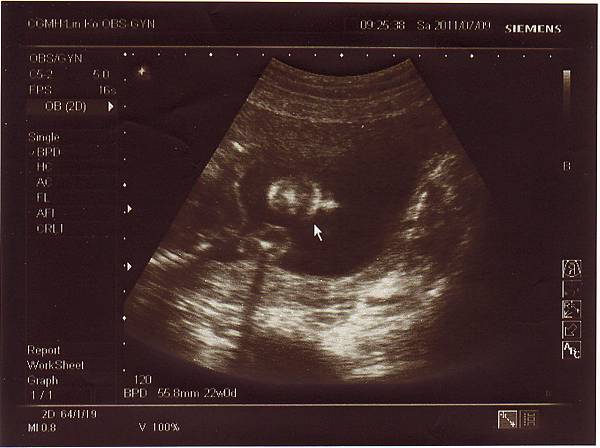

2011.06.25 當天先去超音波室做了仔細的超音波檢查,

檢查心臟.是否兔唇.手腳.肺動脈....等等,

一切都非常正常,也確定是個兔女郎!

兔小妹的手掌~

我是兔小妹的象徵喔!